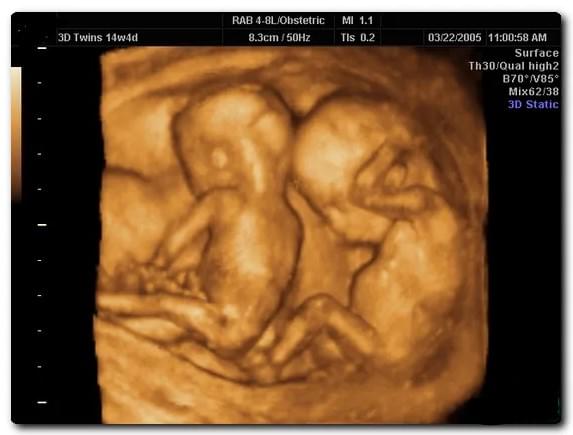

По УЗИ определить однояйцевую беременность наверняка можно только в том случае, если между плодами отсутствует перегородка.

Наверняка определить количество плодов можно только по УЗИ. Исследование покажет также предлежание, размещение, тип и количество плацент и плодных мешков, объем амниотической жидкости, физическое состояние плодов и состояние кровотока в матке.

Из-за повышенной вероятности патологий УЗИ при многоплодной беременности делают чаще, чем при вынашивании одного ребенка. При монозиготной – каждые две недели, при двуяйцевой – 1 раз в месяц.